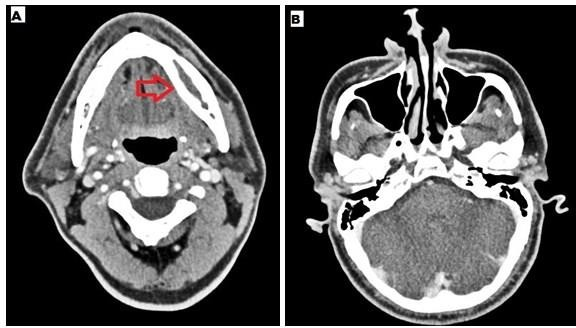

Case 2: He is a 46 years old male presented with pain and swelling of bilateral jaw. He was diagnosed with mild Covid-19 five months ago and received dexamethasone 6mg twice a day followed by once a day for 10 days. There was no history of prior dental procedures. No sinus pain or discharge was present. Sinus endoscopy was unremarkable. HbA1C was 11.2%. Imaging showed bilateral mandibular osteomyelitis (Figure 3) and underwent debridement. Histopathology from the debrided tissue showed broad aseptate fungal hyphae with obtuse angle branching associated with bony and angioinvasion suggestive of mucorales. Few actinomycotic colonies are also found interspersed in the tissue biopsied. Culture was negative for fungal organisms. He was started on injection amphotericin b deoxycholate due to cost constraints and developed acute kidney injury after 5 days. As the disease was limited to bone and he could not tolerate injection amphotericin b for more than 5 days we switched him to tablet posaconazole. Trough concentration was measured after 7 days and found to be 1308 ng/ml. He did well with oral therapy and completed 3 months of posaconazole.

Figure 3 A - CT mandible- bilateral mandibular osteomyelitis with erosion of the cortex, B - CT paranasal sinuses- normal.